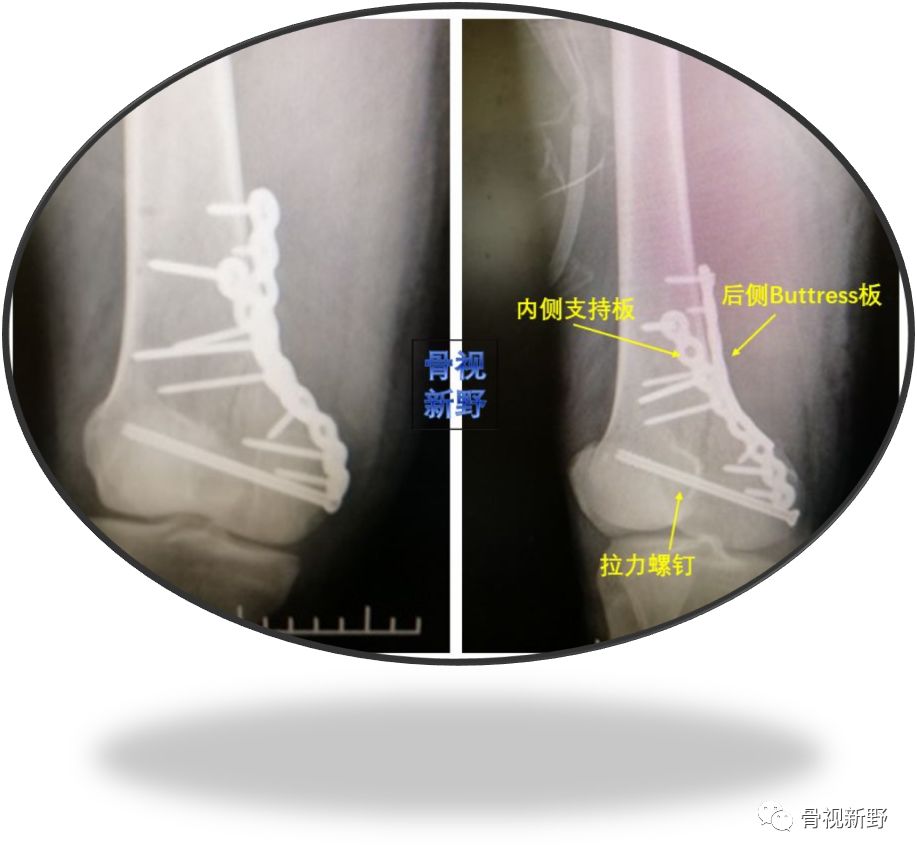

小直径拉力螺钉+侧方支持钢板+后方Buttress重建钢板

小直径拉力螺钉+LCP侧方支持钢板+后方Buttress钢板